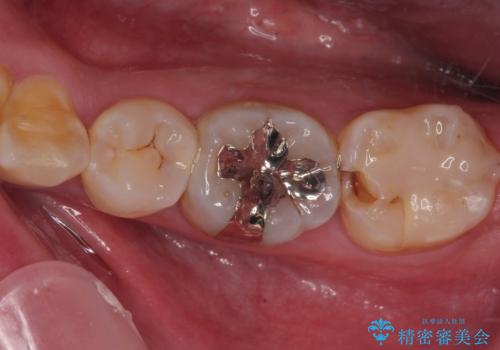

詰め物が欠けて虫歯になってる気がする セラミックインレー修復

- 詰め物が欠けて虫歯になっていることを気にして来院された患者様です。以前に保険のプラスチックの治療を行われていた状況でした。

歯と歯が接しているところの虫歯のため、セラミックの詰め物(セラミックインレー)での治療を進めていくことにしました。